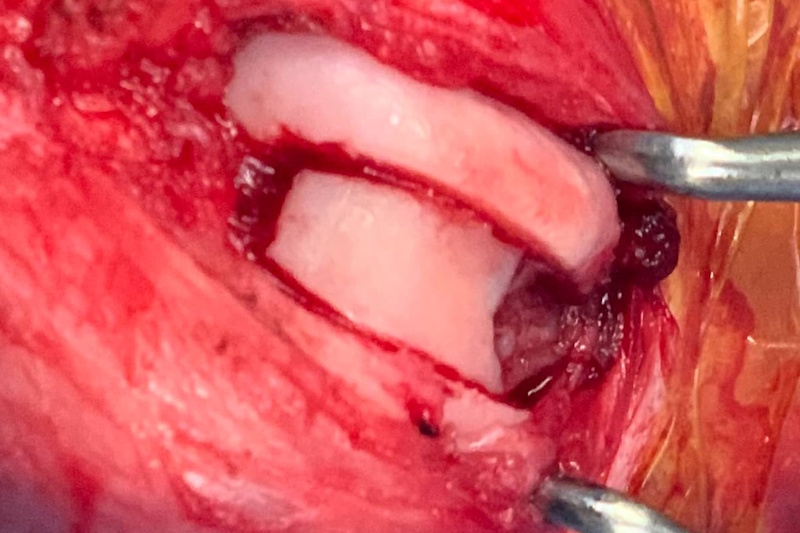

Joint Explore

An incision is made into the joint capsule. This procedure is called an arthrotomy. The joint is lavaged, and the internal structures are examined. Remnants of the damaged cranial cruciate ligament are removed as it serves no purpose after the joint has been stabilized, and the remnants could create a future source of pain. The medial and lateral menisci are cartilage pads that help to transfer weight from the femur to the tibia. These cartilages are examined. If damaged, then the damaged portion is removed (partial meniscectomy), or the entire meniscus may be removed (complete meniscectomy). The joint is lavaged and the joint capsule is sutured closed with a dissolvable suture.

Osteochondritis dissecans (OCD) is a developmental condition that arises due to a disturbance in the normal differentiation of cartilage cells resulting in failure of endochondral ossification (essential process during foetal development of skeletal system resulting in bone formation).

In dogs that grow very quickly, the rapid cartilage growth can outstrip its own blood supply causing abnormal cartilage development resulting in lameness, pain and subsequent osteoarthritis. In some cases, flaps of diseased cartilage become separated from the remaining cartilage surface. This is called osteochondritis dissecans.

OCD lesion of the canine stifle highlighted with a blue dotted line

How Is Stifle OCD Treated?

- Surgical Removal of the Cartilage Flap

- SynaCart